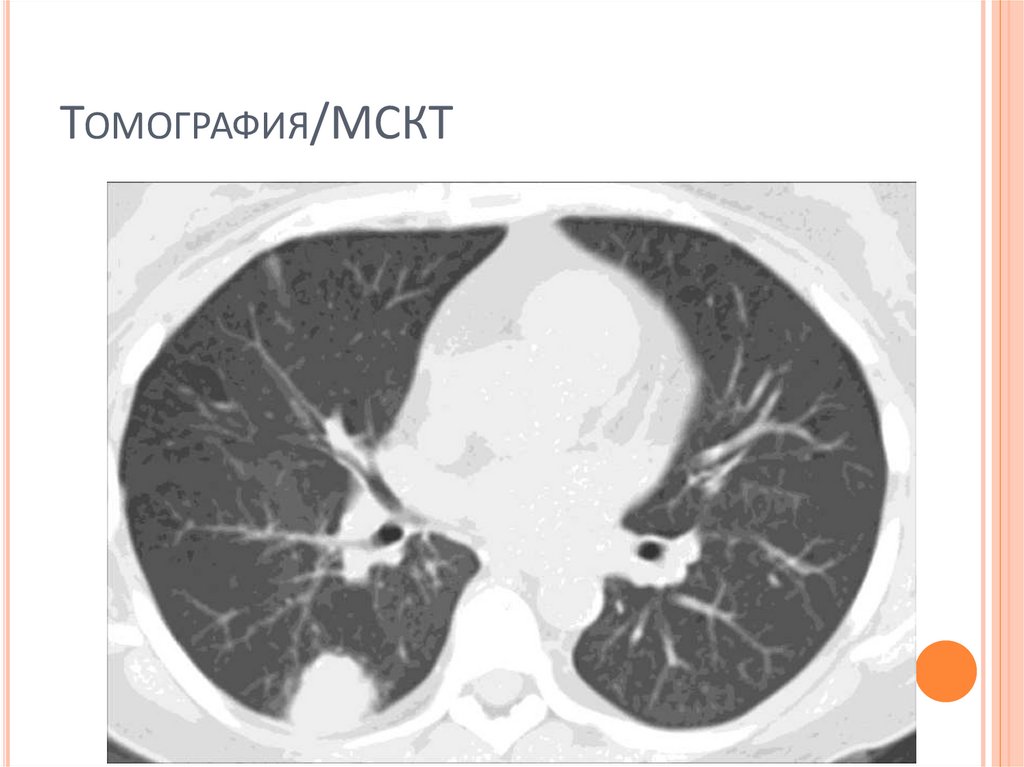

43. Томография/МСКТ

ТОМОГРАФИЯ/МСКТ

Позволяет точнее определить локализацию

патологической тени

Плотность патологической тени

Структуру патологической тени